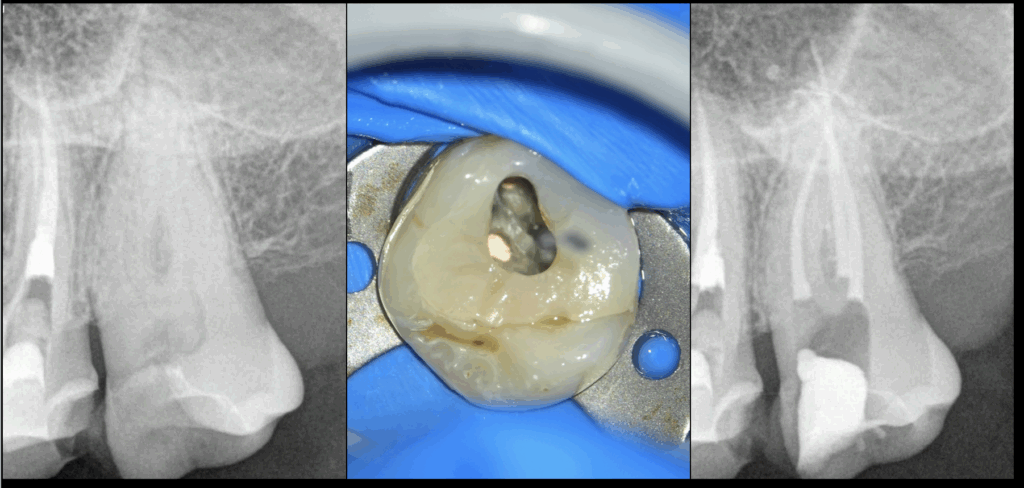

🦷 Traitement initial de la 27 !

Simple ? Basique ?

🤔 𝐏𝐚𝐬 𝐪𝐮𝐚𝐧𝐝 𝐥𝐚 𝐥𝐢𝐦𝐢𝐭𝐚𝐭𝐢𝐨𝐧 𝐝’𝐨𝐮𝐯𝐞𝐫𝐭𝐮𝐫𝐞 𝐛𝐮𝐜𝐜𝐚𝐥𝐞 𝐞𝐬𝐭 𝐚̀ 𝟏 𝐝𝐨𝐢𝐠𝐭 !

➡️ Ce qui qualifie ce cas de « très difficile » d’après les guidelines d’évaluation des difficultés par l’AAE (Association Américaine des Endodontistes).

🪑 𝐄𝐧 𝐫𝐞́𝐬𝐮𝐦𝐞́ : 𝐜̧𝐚 𝐩𝐞𝐮𝐭 𝐬𝐞𝐦𝐛𝐥𝐞𝐫 𝐬𝐢𝐦𝐩𝐥𝐞 𝐬𝐮𝐫 𝐮𝐧𝐞 𝐫𝐚𝐝𝐢𝐨 𝐞𝐭 𝐞̂𝐭𝐫𝐞 𝐭𝐞𝐫𝐫𝐢𝐛𝐥𝐞𝐦𝐞𝐧𝐭 𝐝𝐢𝐟𝐟𝐢𝐜𝐢𝐥𝐞 𝐬𝐮𝐫 𝐥𝐞 𝐟𝐚𝐮𝐭𝐞𝐮𝐢𝐥 ! 😉